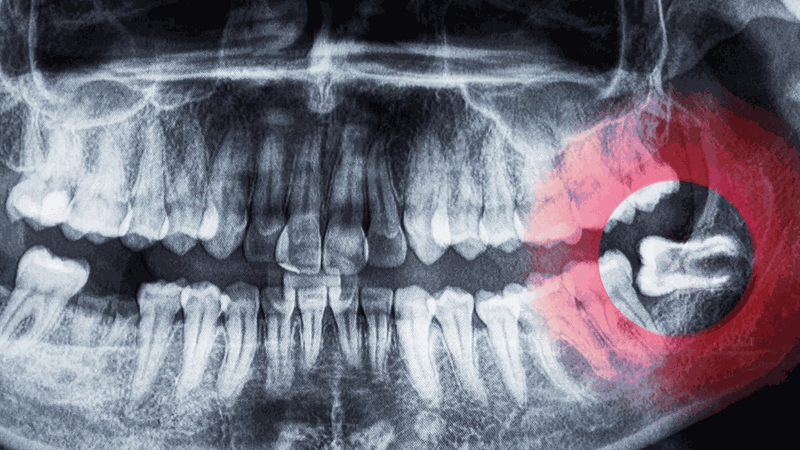

Răng khôn (còn gọi là răng số 8 hoặc răng hàm lớn thứ ba) là chiếc răng cuối cùng mọc ở phía sau mỗi hàm, thường xuất hiện khi một người từ 17 đến 25 tuổi. Đây là răng mọc muộn nhất trong hàm, khi các răng khác đã ổn định, do đó, răng khôn thường không có đủ chỗ để mọc thẳng và thường gây ra các vấn đề như đau nhức, viêm nhiễm, hoặc răng mọc lệch.

Răng khôn bị sâu có nên nhổ hay không phụ thuộc vào nhiều yếu tố khác nhau. Đầu tiên, bác sĩ sẽ thực hiện thăm khám lâm sàng và chụp X-quang để xác định mức độ sâu của răng. Nếu răng khôn mới bị sâu nhẹ và vẫn còn khả năng phục hồi, bác sĩ có thể chỉ định phương pháp trám răng.

Ngược lại, nếu tình trạng sâu răng đã nghiêm trọng, ảnh hưởng đến tủy hoặc có nguy cơ lây lan sang các răng lân cận, việc nhổ răng khôn là lựa chọn cần thiết. Bên cạnh đó, các trường hợp răng khôn mọc lệch, mọc ngầm hoặc kẹt trong nướu cũng cần được nhổ bỏ để tránh các biến chứng về sức khỏe.